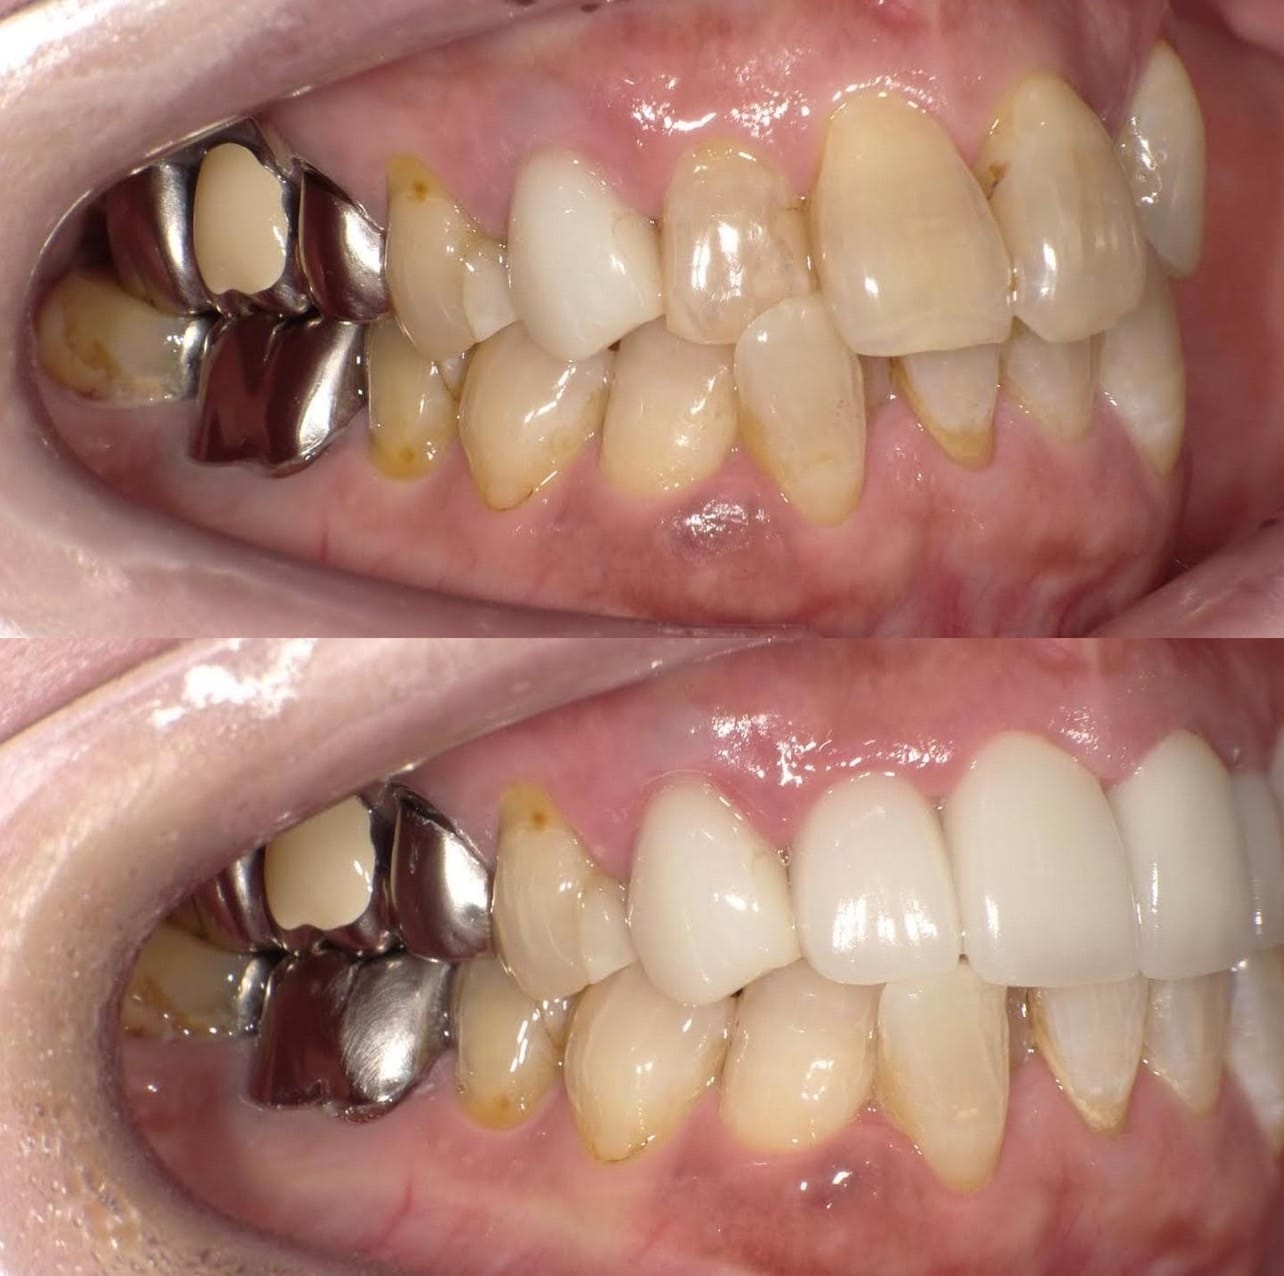

「ずっと放置してしまっていた。今回はちゃんとしっかり治したい」ということで、強い意志をもって来院してくださった患者様の症例です。

インプラント治療、セラミック治療、歯周病治療により、審美性と機能、咬みあわせの再建を行いました。

患者様は咬みあわせの確立により、食事もしやすく、普段の顎関節の状況も良くなり、機能の回復にも満足してくださり、また審美性も喜んでくださいました。

放置期間が長くだいぶ骨が溶けてしまっていたので、前歯部のインプラントは骨の再生療法などが必要だったりしましたが、患者様が治療への前向きな姿勢をだしてくださっていましたので期間も最短で終わりました。

一度放置してしまうと、億劫になってしまってなかなか行動に移すのは難しいと思いますが、少しでも早く治してあげた方が毎日の食事も楽になりますし、お顔の見栄えもお顔の骨格の歪みも改善します。